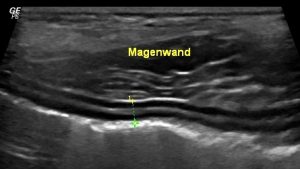

Einsatz der Sonographie in der Inneren Medizin

Die sonographische Untersuchung wird bei Verdacht auf Flüssigkeitsansammlungen in einer Körperhöhle sowie bei morphologischen

Veränderungen an folgenden Organen durchgeführt:

- Verdauungstrakt (Magen-Darm-Trakt, inkl. Lymphknoten)